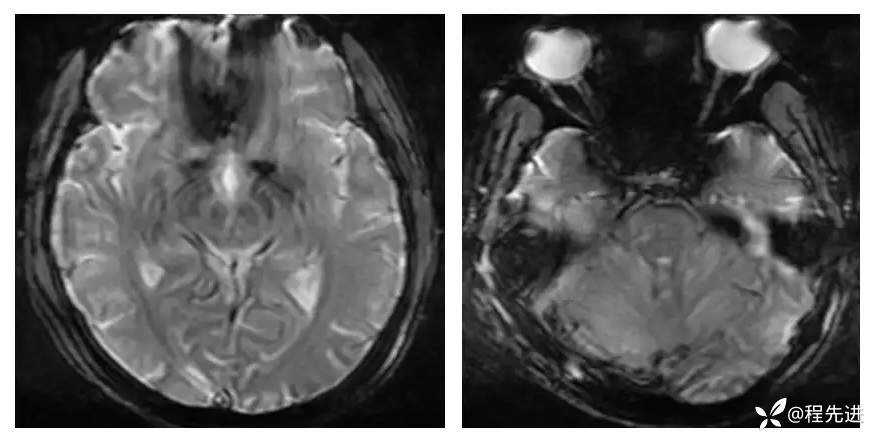

【现病史及既往史】:孕期38周,蛋白尿10天,血压升高6天,剖腹产后一天出现头晕,头痛,嗜睡。既往糖尿病史

查体:不配合,血压波动,130-157/85-109mmHg

影像检查: